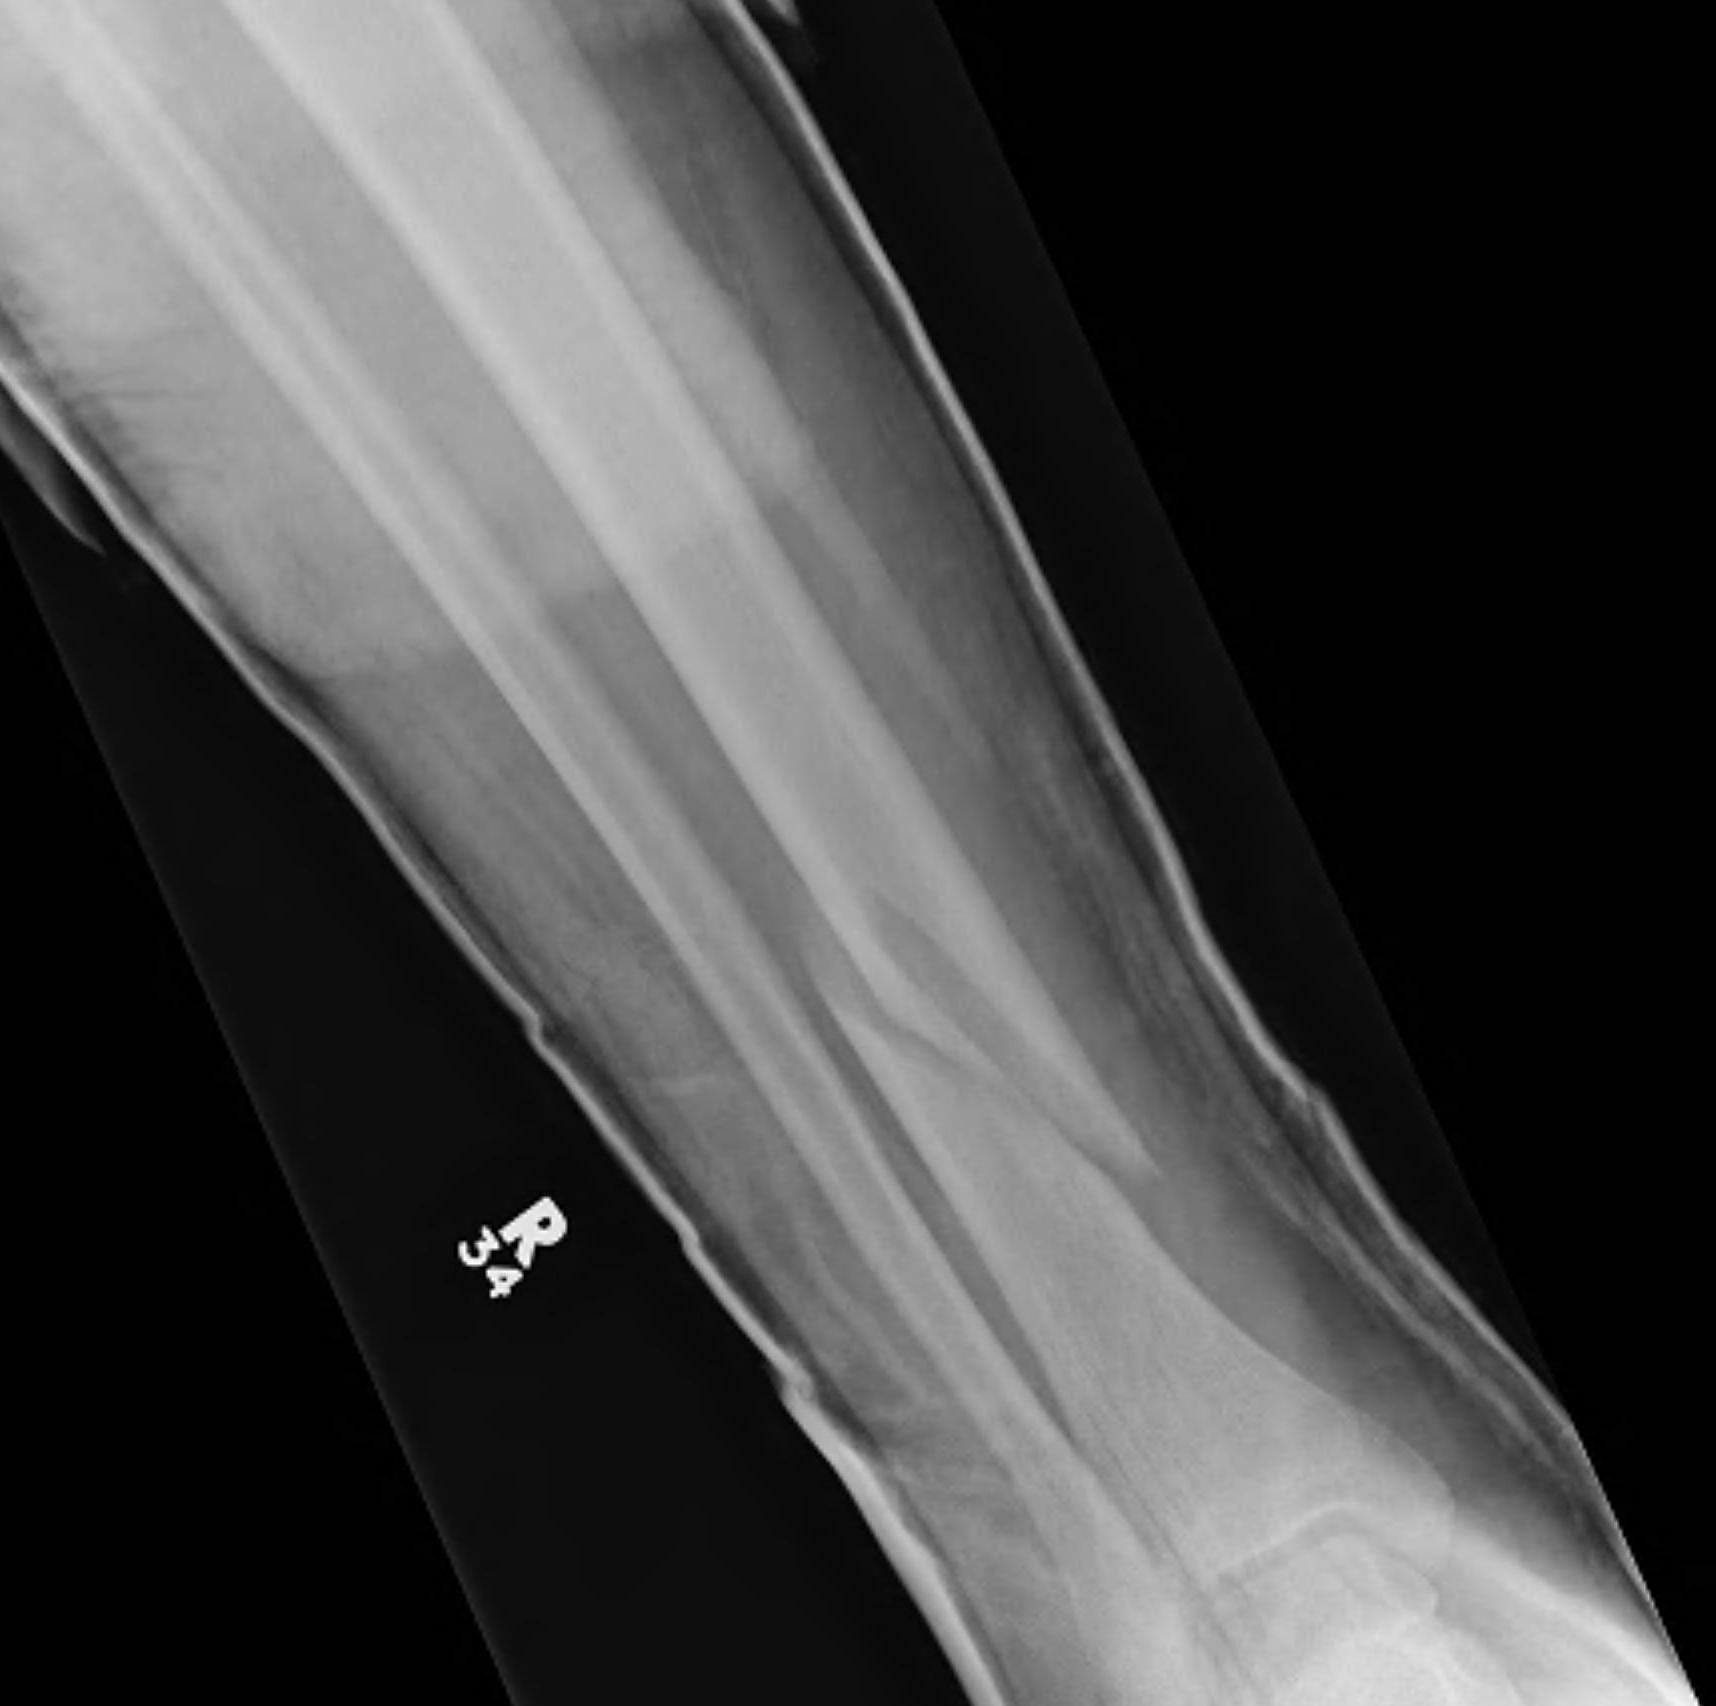

Metaphyseal

Extra-articular

Intra-articular Extension

Intra-medullary Nail

Indications

- wounds / soft tissues not suitable to plate

- relatively stable

- sufficient distal bone